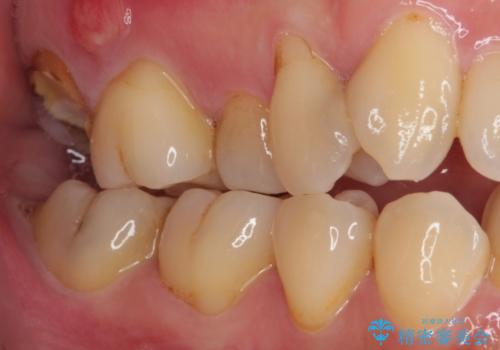

外側を向いている上顎の奥歯は歯ブラシが十分に届かないため、むし歯となるケースが多いのですが、今回むし歯となってしまった歯がそれで、ボロボロになって根だけが残っている状態でした。

患者様と相談し、抜歯をした上でインプラントによる補綴治療を行うこととしました。